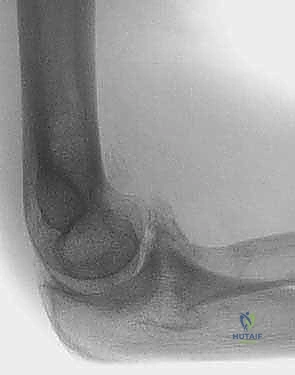

- الأشعة السينية (X-rays): الفحص الأساسي لرؤية العظام. تُظهر الأشعة السينية بوضوح تضيق المسافة المفصلية، وجود النتوءات العظمية (المهماز العظمي) في الحفرة الزجية والإكليلية، والأجسام الحرة الكبيرة.

- الأشعة المقطعية ثلاثية الأبعاد (3D CT Scan): تُعد الأداة الأهم للتخطيط الجراحي لعملية أوتبيردج-كاشيواجي. توفر خريطة دقيقة ثلاثية الأبعاد لحجم وموقع النتوءات العظمية، وتساعد الدكتور هطيف على تحديد كمية العظام التي يجب إزالتها بدقة مليمترية.

يتكون الجزء البعيد من عظم العضد من لُقمتين: البكرة الإنسية (Medial Trochlea) والرؤيس الوحشي (Lateral Capitellum). فوق هذه الأسطح المفصلية مباشرة، توجد تجاويف هامة جداً:

* الحفرة الإكليلية (Coronoid Fossa): تقع من الأمام، وتستوعب الناتئ الإكليلي (Coronoid Process) لعظمة الزند أثناء الثني الشديد للكوع.

* الحفرة الزجية (Olecranon Fossa): تقع من الخلف، وتستوعب الناتئ الزجي (Olecranon Process) لعظمة الزند أثناء الفرد (المد) الكامل للكوع.

في حالات خشونة الكوع، تمتلئ هذه الحفر بالنتوءات العظمية والأنسجة الليفية، مما يمنع العظام من الدخول في أماكنها الطبيعية، وهذا هو التفسير الميكانيكي لعدم قدرة المريض على فرد أو ثني ذراعه بالكامل.